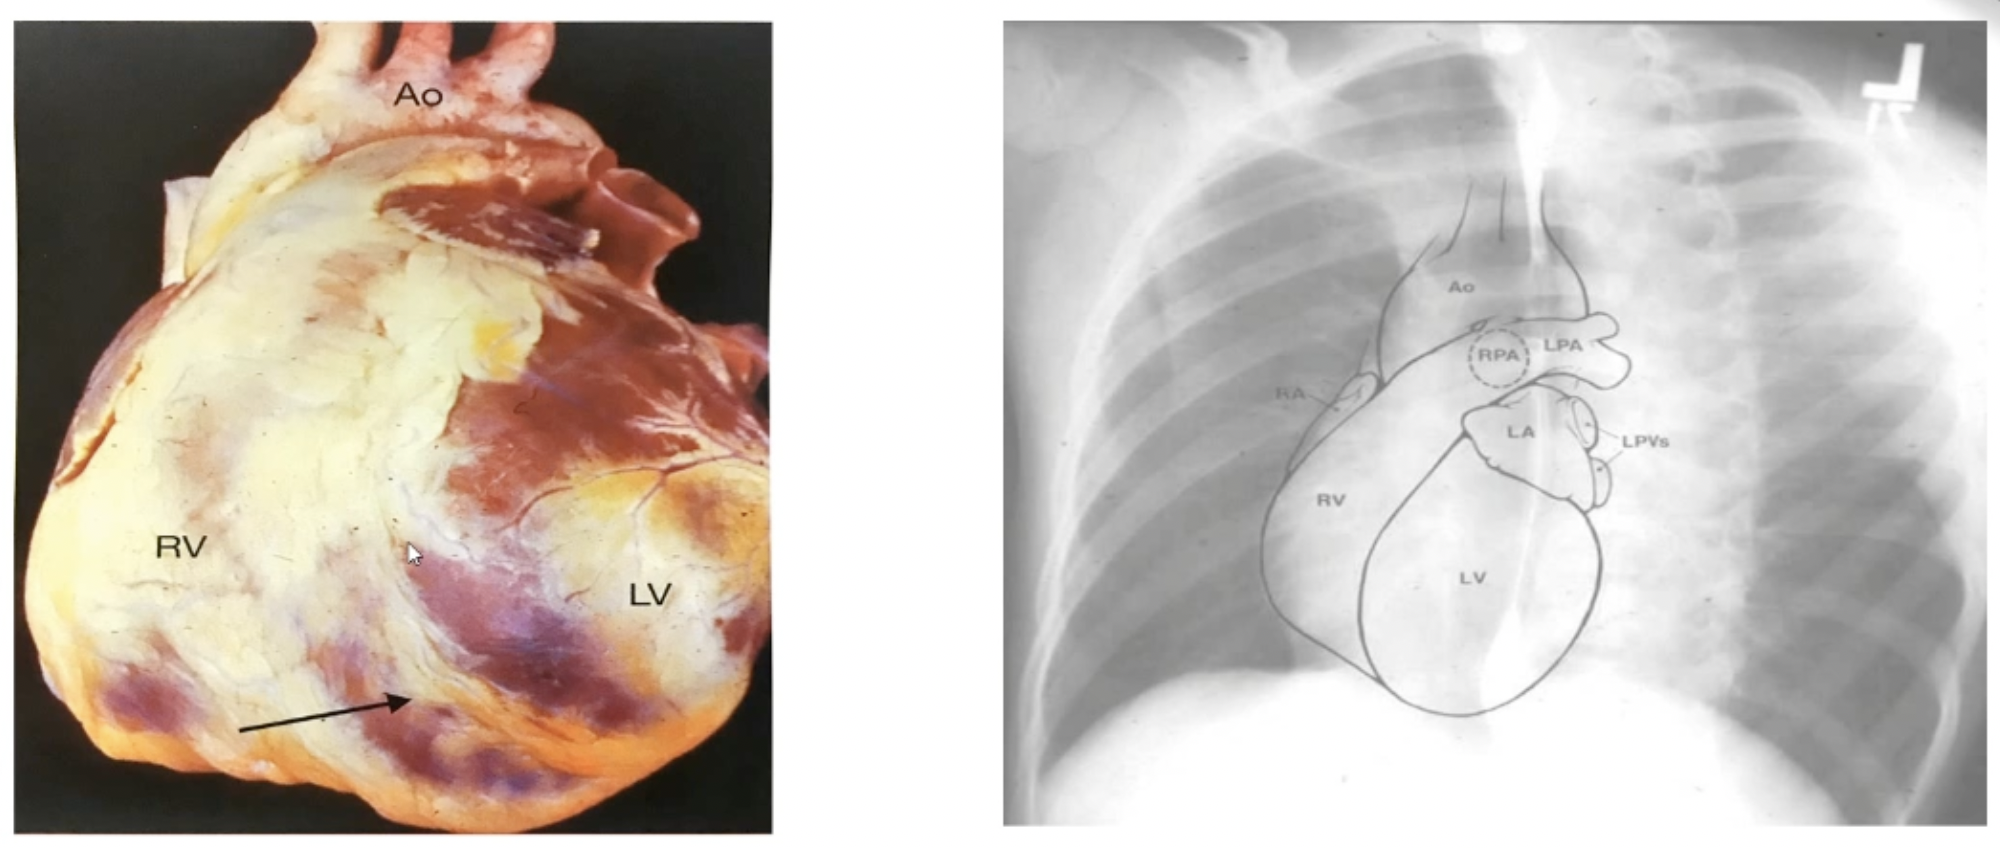

# 左前斜 LAO

- 观察左心室、右心房、右心室、主动脉弓